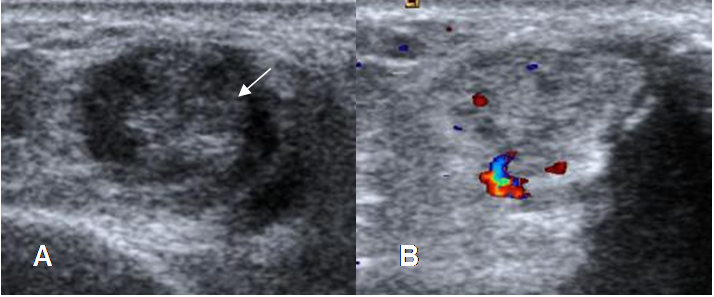

Fig 67. Tendinitis crónica.

A: Ecografía axial. Engrosamiento de los tendones peroneos, por inflamación crónica, los

cuales están además rodeados por líquido.

B: Doppler axial. Tendón peroneo engrosado y con aumento de la señal doppler, por neovascularización.